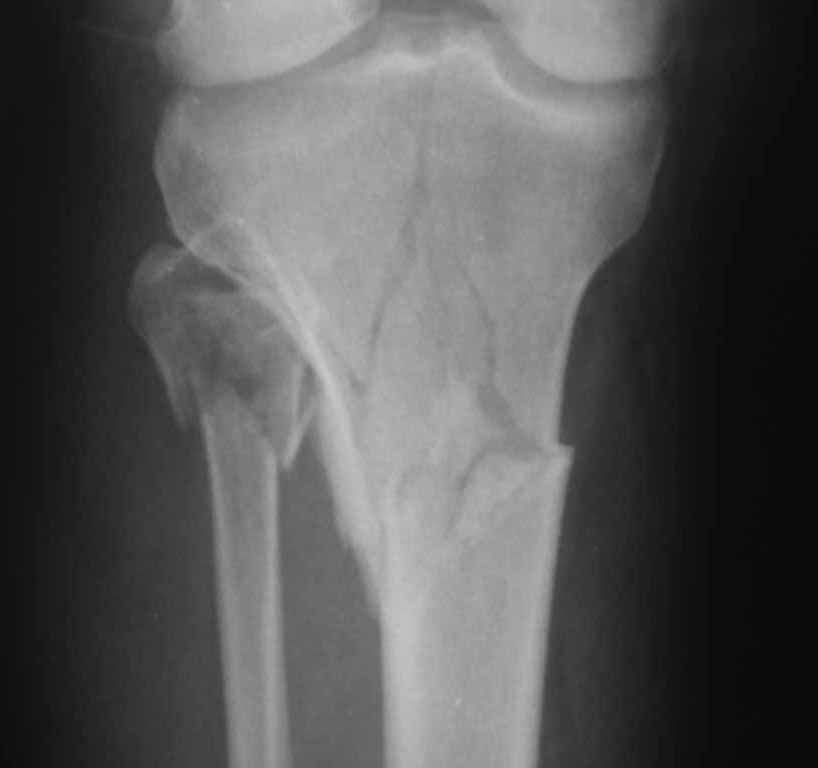

Двухколоннный перелом тибиал плато с вовлечением проксимального диафиза. Внутрисуставной компонент без смещения, и такой перелом можно лечить любым из описанных методов, о которых говорят наши коллеги.

Удобно аппаратом Илизарова или интрамедуллярным гвоздем. Гвозди не так сложно, как пугают, тем более Александр готов помощь с методичкой. Сперва надо установить компрессирующие шурупы на мыщелки. Давно отказались в пользу 3.5-4.0 мм кортикальных вместо толстых спонгиозных, потому что не доказаны преимущества толстых шурупов. Тонкие шурупы в субхондральной зоне смотрятся намного элегантнее, чем толстые 6.5.

Как понял, аппарат Илизарова не рассматривается предпочтительным для фиксации методом, хотя на фоне отека было бы идеальным для данного перелома. Для пластины требуется идеальная кожа, иначе наличие “суперсовременных имплантов” не поможет, и могут развиться серьезные осложнения.

Частая ошибка, когда фиксацию двух колонного перелома проводят одиночной пластиной, т.е с одной стороны, и такая фиксация не удерживает, происходит вторичноое смещение. Необходимо нейтрализовать второй пластиной или дополнительным наружным фиксатором.

Если у вас, кроме пластины, нет другого альтернативного варианта, тогда, учитывая мягкотканые проблемы с наружной стороны, я бы рекомендовал операцию делать в два этапа. Преимущества, сперва репозиция и фиксация перелома с медиальной стороны, а затем, после улучшения состояния мягких тканей, зафиксировать с латеральной стороны. Современные пластины имеют латеральный Jig для перкутанных мини доступов.

Кстати, коллеги правы для уточнения характера перелома надо делать Компьютерную Томографию.

В приложении этапы фиксации Both Column Fx и пластиной Synthes для плеча при переломе медиального мыщелка.